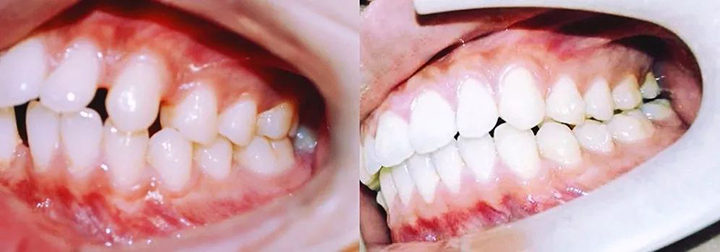

上图就是矫正前后牙齿的对比照,欢迎观看右边照片多一点!

那就是54副牙套带来的一口重生的白牙。

『 排齐上下前牙,关闭前牙散在间隙 』

——矫正目标临近达成,再有4副就能收工,完美!

完整的观察一下目前达到的矫治效果,会发现真的很棒!